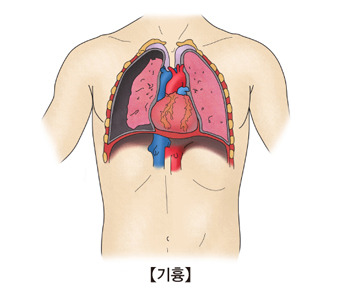

폐렴이 진행되면 패혈증이나 쇼크가 발생할 수 있습니다. 국소적인 합병증으로 흉수, 농흉, 폐농양 등이 생길 수 있습니다. 모든 폐렴 환자에게 합병증이 동반되는 것은 아닙니다. 하지만 고위험군 환자는 합병증이 생길 확률이 높으므로 주의가 필요합니다.